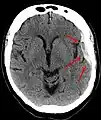

Sur le scanner crânien, fait sans injection de produit de contraste, l'hématome sous-dural se présente habituellement sous une forme de croissant, dont la concavité suit la courbe du cerveau, stoppé seulement par les réflexions durales telles que la faux du cerveau et le tentorium. Cependant ils peuvent avoir une forme convexe, spécialement tout au début du saignement, ce qui peut les faire confondre avec les hémorragies épidurales (hématome extradural). Le sang peut être vu comme une densité stratifiée tout au long du tentorium. Dans les cas chroniques, on peut voir l'effacement des sillons ou le déplacement médian de la jonction substance blanche/substance grise, mais le sang peut avoir une densité très proche de celle du tissu cérébral (isodense), ce qui peut masquer l'hématome.